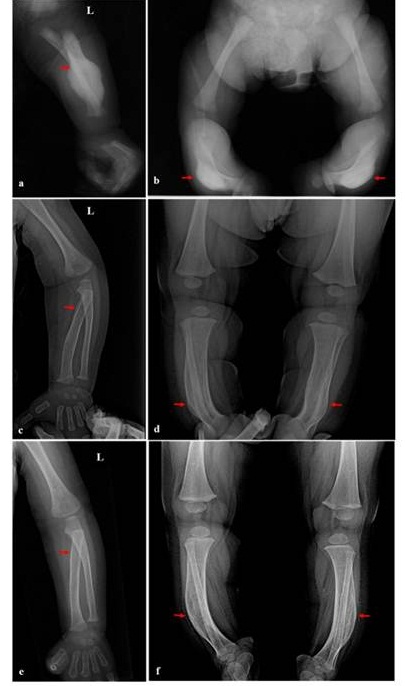

La radiografía simple neonatal de miembros superiores e inferiores (figuras 2a y 2b) evidenció la periostitis e hiperostosis cortical con curvatura anterior del radio izquierdo, asociado con un importante engrosamiento cortical en la diáfisis de las tibias derecha e izquierda, e inflamación del tejido blando circundante. La radiografía simple de cráneo no evidenció microfracturas o engrosamiento cortical de la bóveda craneal. La ecografía abdominal mostró riñones de características conservadas, así como uréteres y vejiga sin alteraciones.

Radiografías anterolaterales simples del probando (individuo IV-11) al nacimiento. a) Radio izquierdo, b) tibia derecha e izquierda. A los tres meses; c) radio izquierdo, que con una marcada disminución perióstica; d) tibias que evidencian una moderada reducción cortical de la diáfisis. A los ocho meses, e) y f) aumento del espacio medular propio de la fase de remodelación en el radio izquierdo y tibias, respectivamente.

La evaluación radiográfica de seguimiento en la consulta externa de los tres meses de edad (figuras 2c y 2d) mostró una disminución de la hiperostosis cortical. La porción proximal de la diáfisis radial izquierda evidenció un ligero engrosamiento interno de la corteza. Las tibias derecha e izquierda exhibieron una marcada disminución perióstica e inflamación del tejido blando circundante. A los ocho meses de edad (figuras 2e y 2f) hubo un aumento del espacio medular radial izquierdo y tibial bilateral, respectivamente.